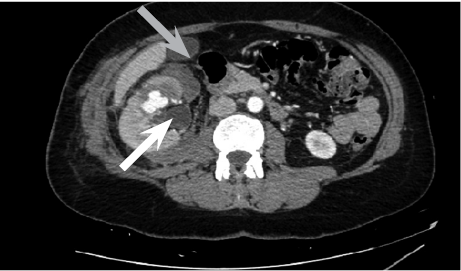

Cause of hematuria had to be determined, therefore urgent contrast enhanced computed tomography was performed (Figure 2) – contrast extravazation was found on the lower third of the right kidney (area of surgery), along with subcapsular hemathoma. Right hydroureteronephrosis and fluid in pelvis were observed. Blood clots and a small amount of contrast in the bladder were seen.

Figure 2. Contrast extravazation was found on the lower third of the right kidney (white arrow), subcapsular hemathoma (grey arrow)